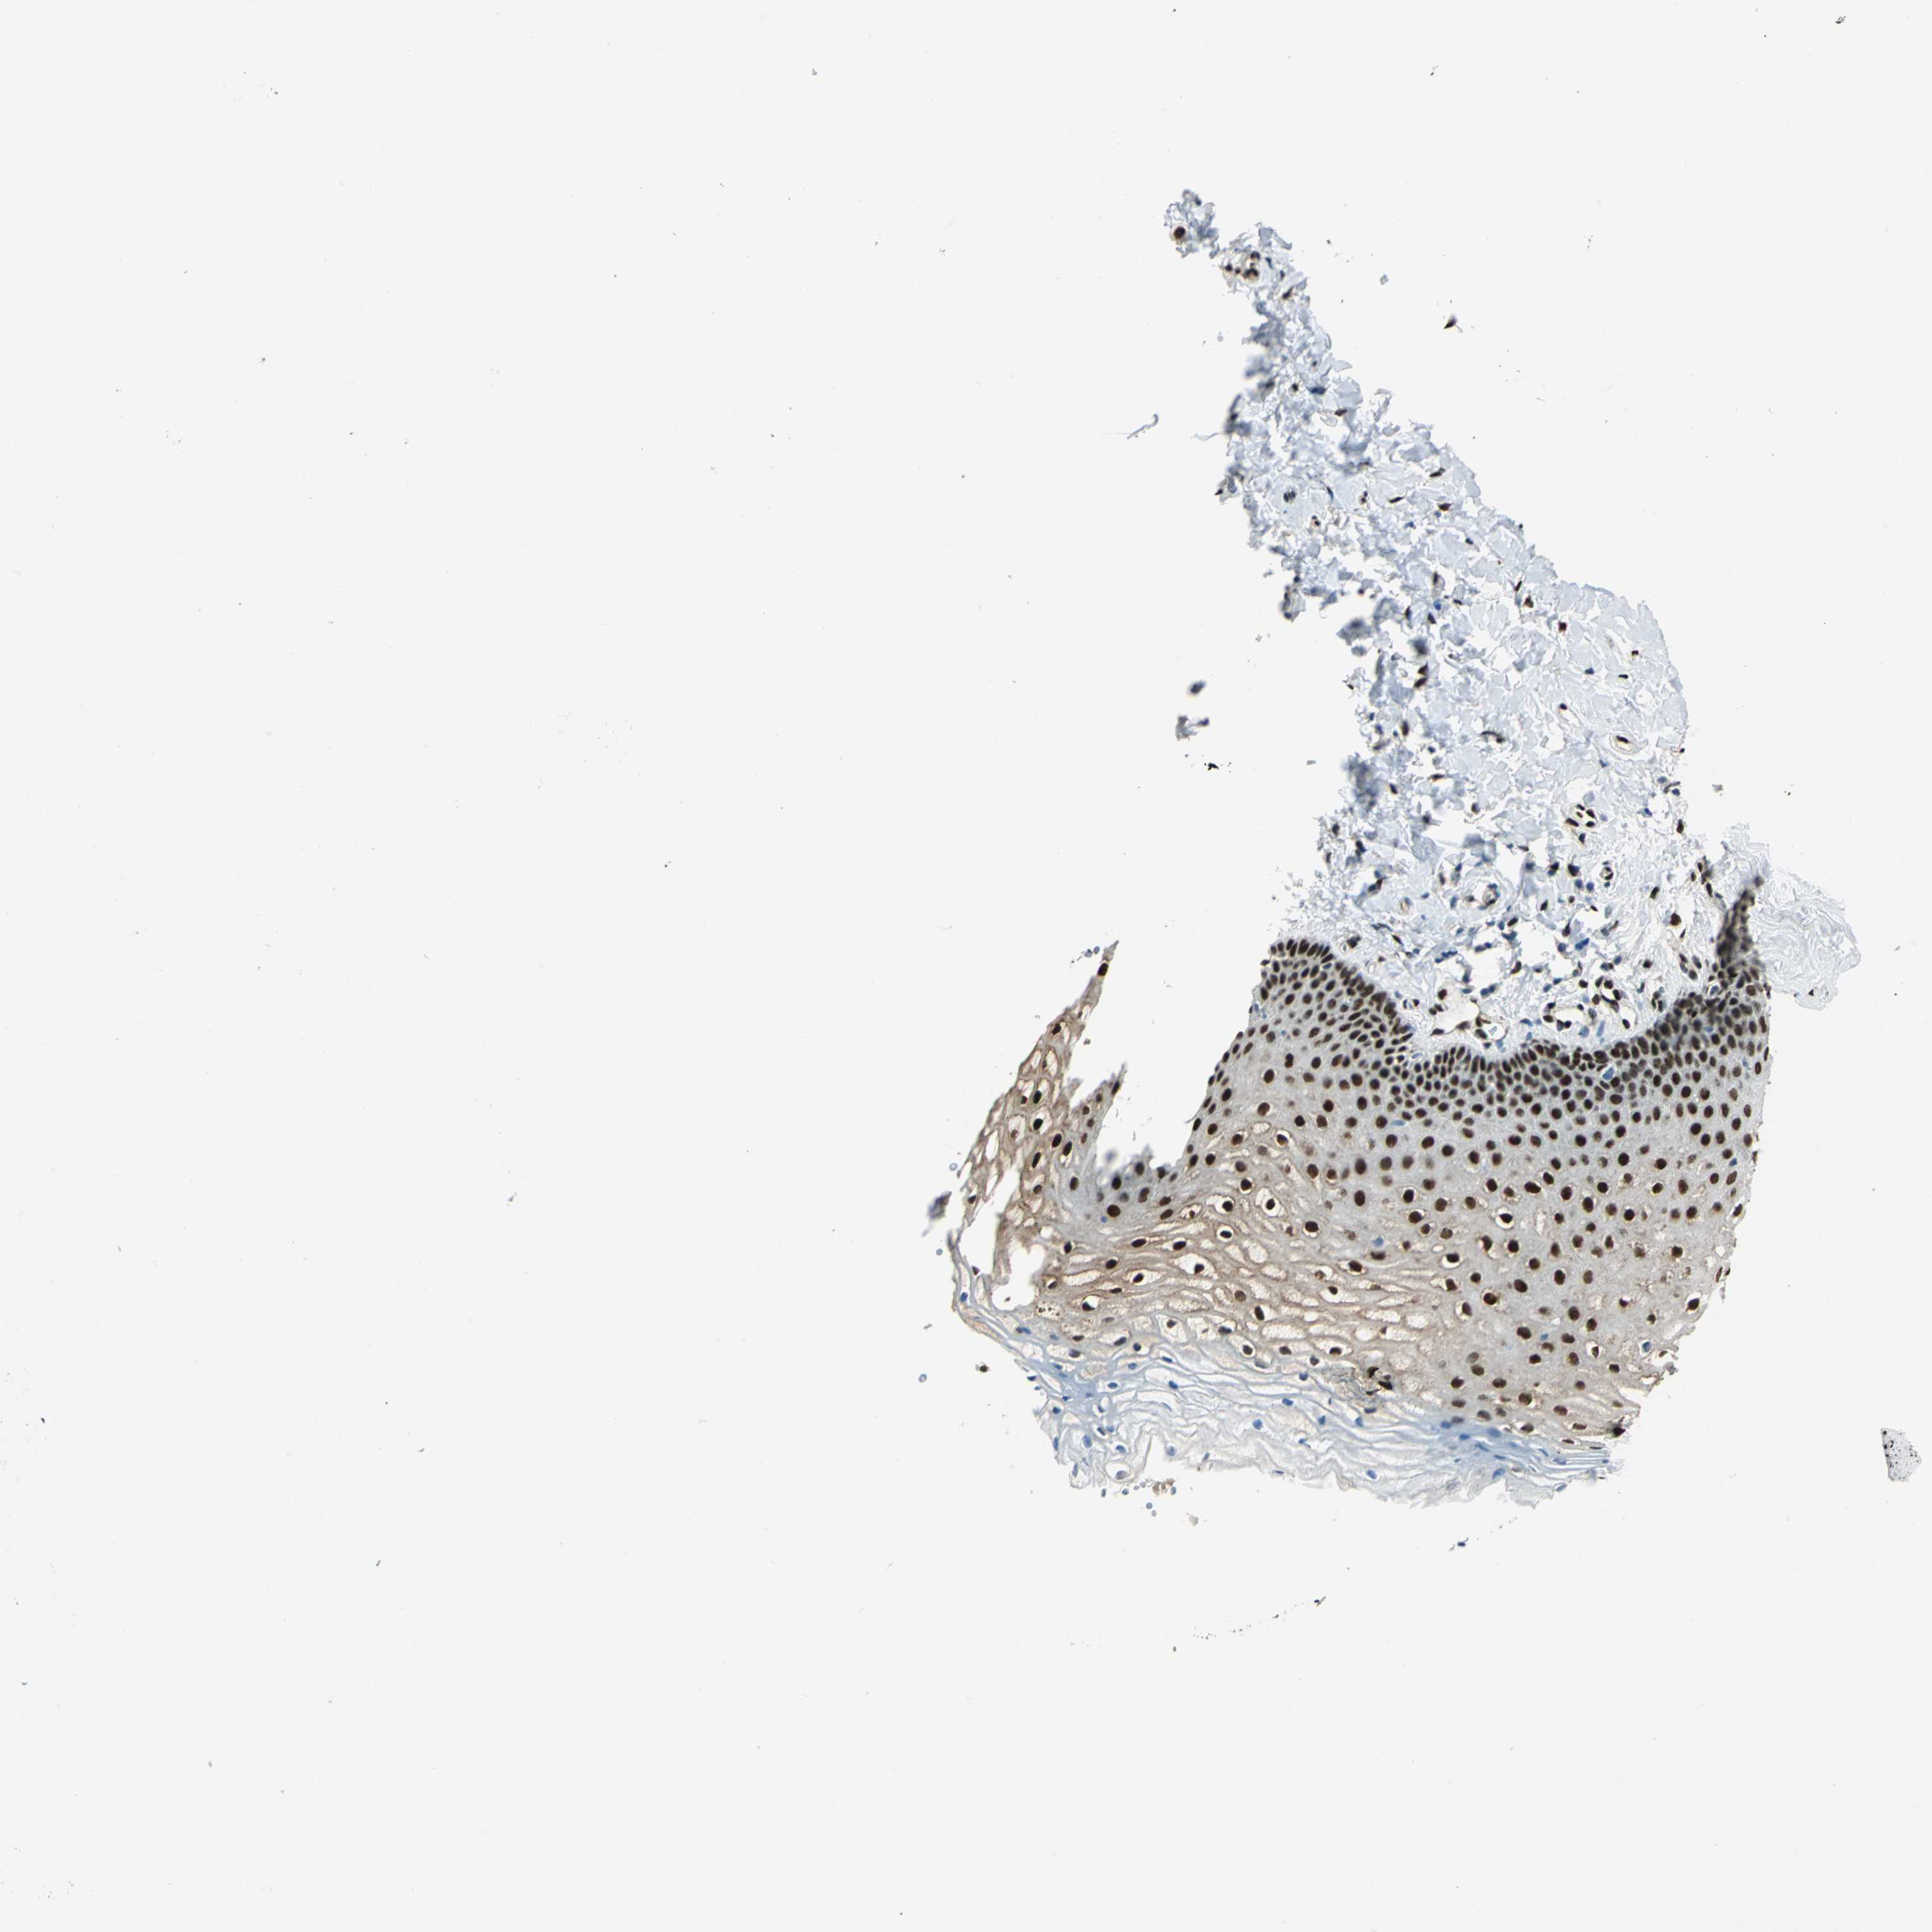

VAGINA - Antibody stainingi

Antibody staining in the annotated cell types in the current human tissue is reported as not detected, low, medium, or high, based on conventional immunohistochemistry profiling in selected tissues. This score is based on the combination of the staining intensity and fraction of stained cells.

Each image is clickable and will lead to virtual microscopy that enables deeper exploration of all samples and also displays staining intensity scores, fraction scores and subcellular localization as well as patient and tissue information for each sample.

Antibody HPA006111Antibody HPA008884

Squamous epithelial cells HighMedium